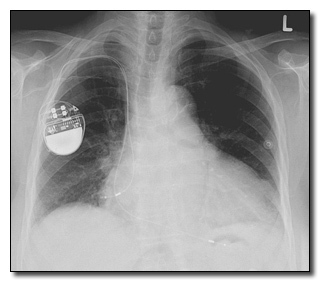

Everything from your car to your blender is getting upgraded with a computer chip these days. Medical implants like pacemakers are no exception. Since they need to be updated somewhat remotely anyway (otherwise all maintenance would involve major surgery), they do have limited outside connectivity, allowing doctors to access your stored medical history, your name and address and your doctor's name and address. Oh, and a skilled hacker can access all of it, too.

That's right: They can hack your goddamn heart.

And as if we need to say it: Obviously they can remotely stop it beating while they're in there.

In some devices, like an implanted defibrillator, which shocks your heart back into activity if it ever seizes up, hackers can remotely shut off the device and wait for you to die or, if they just ain't got all day, send it into test mode instead -- where the pacemaker repeatedly delivers powerful, fatal shocks to the heart even when it's already beating just fine.

Via Wikimedia Commons